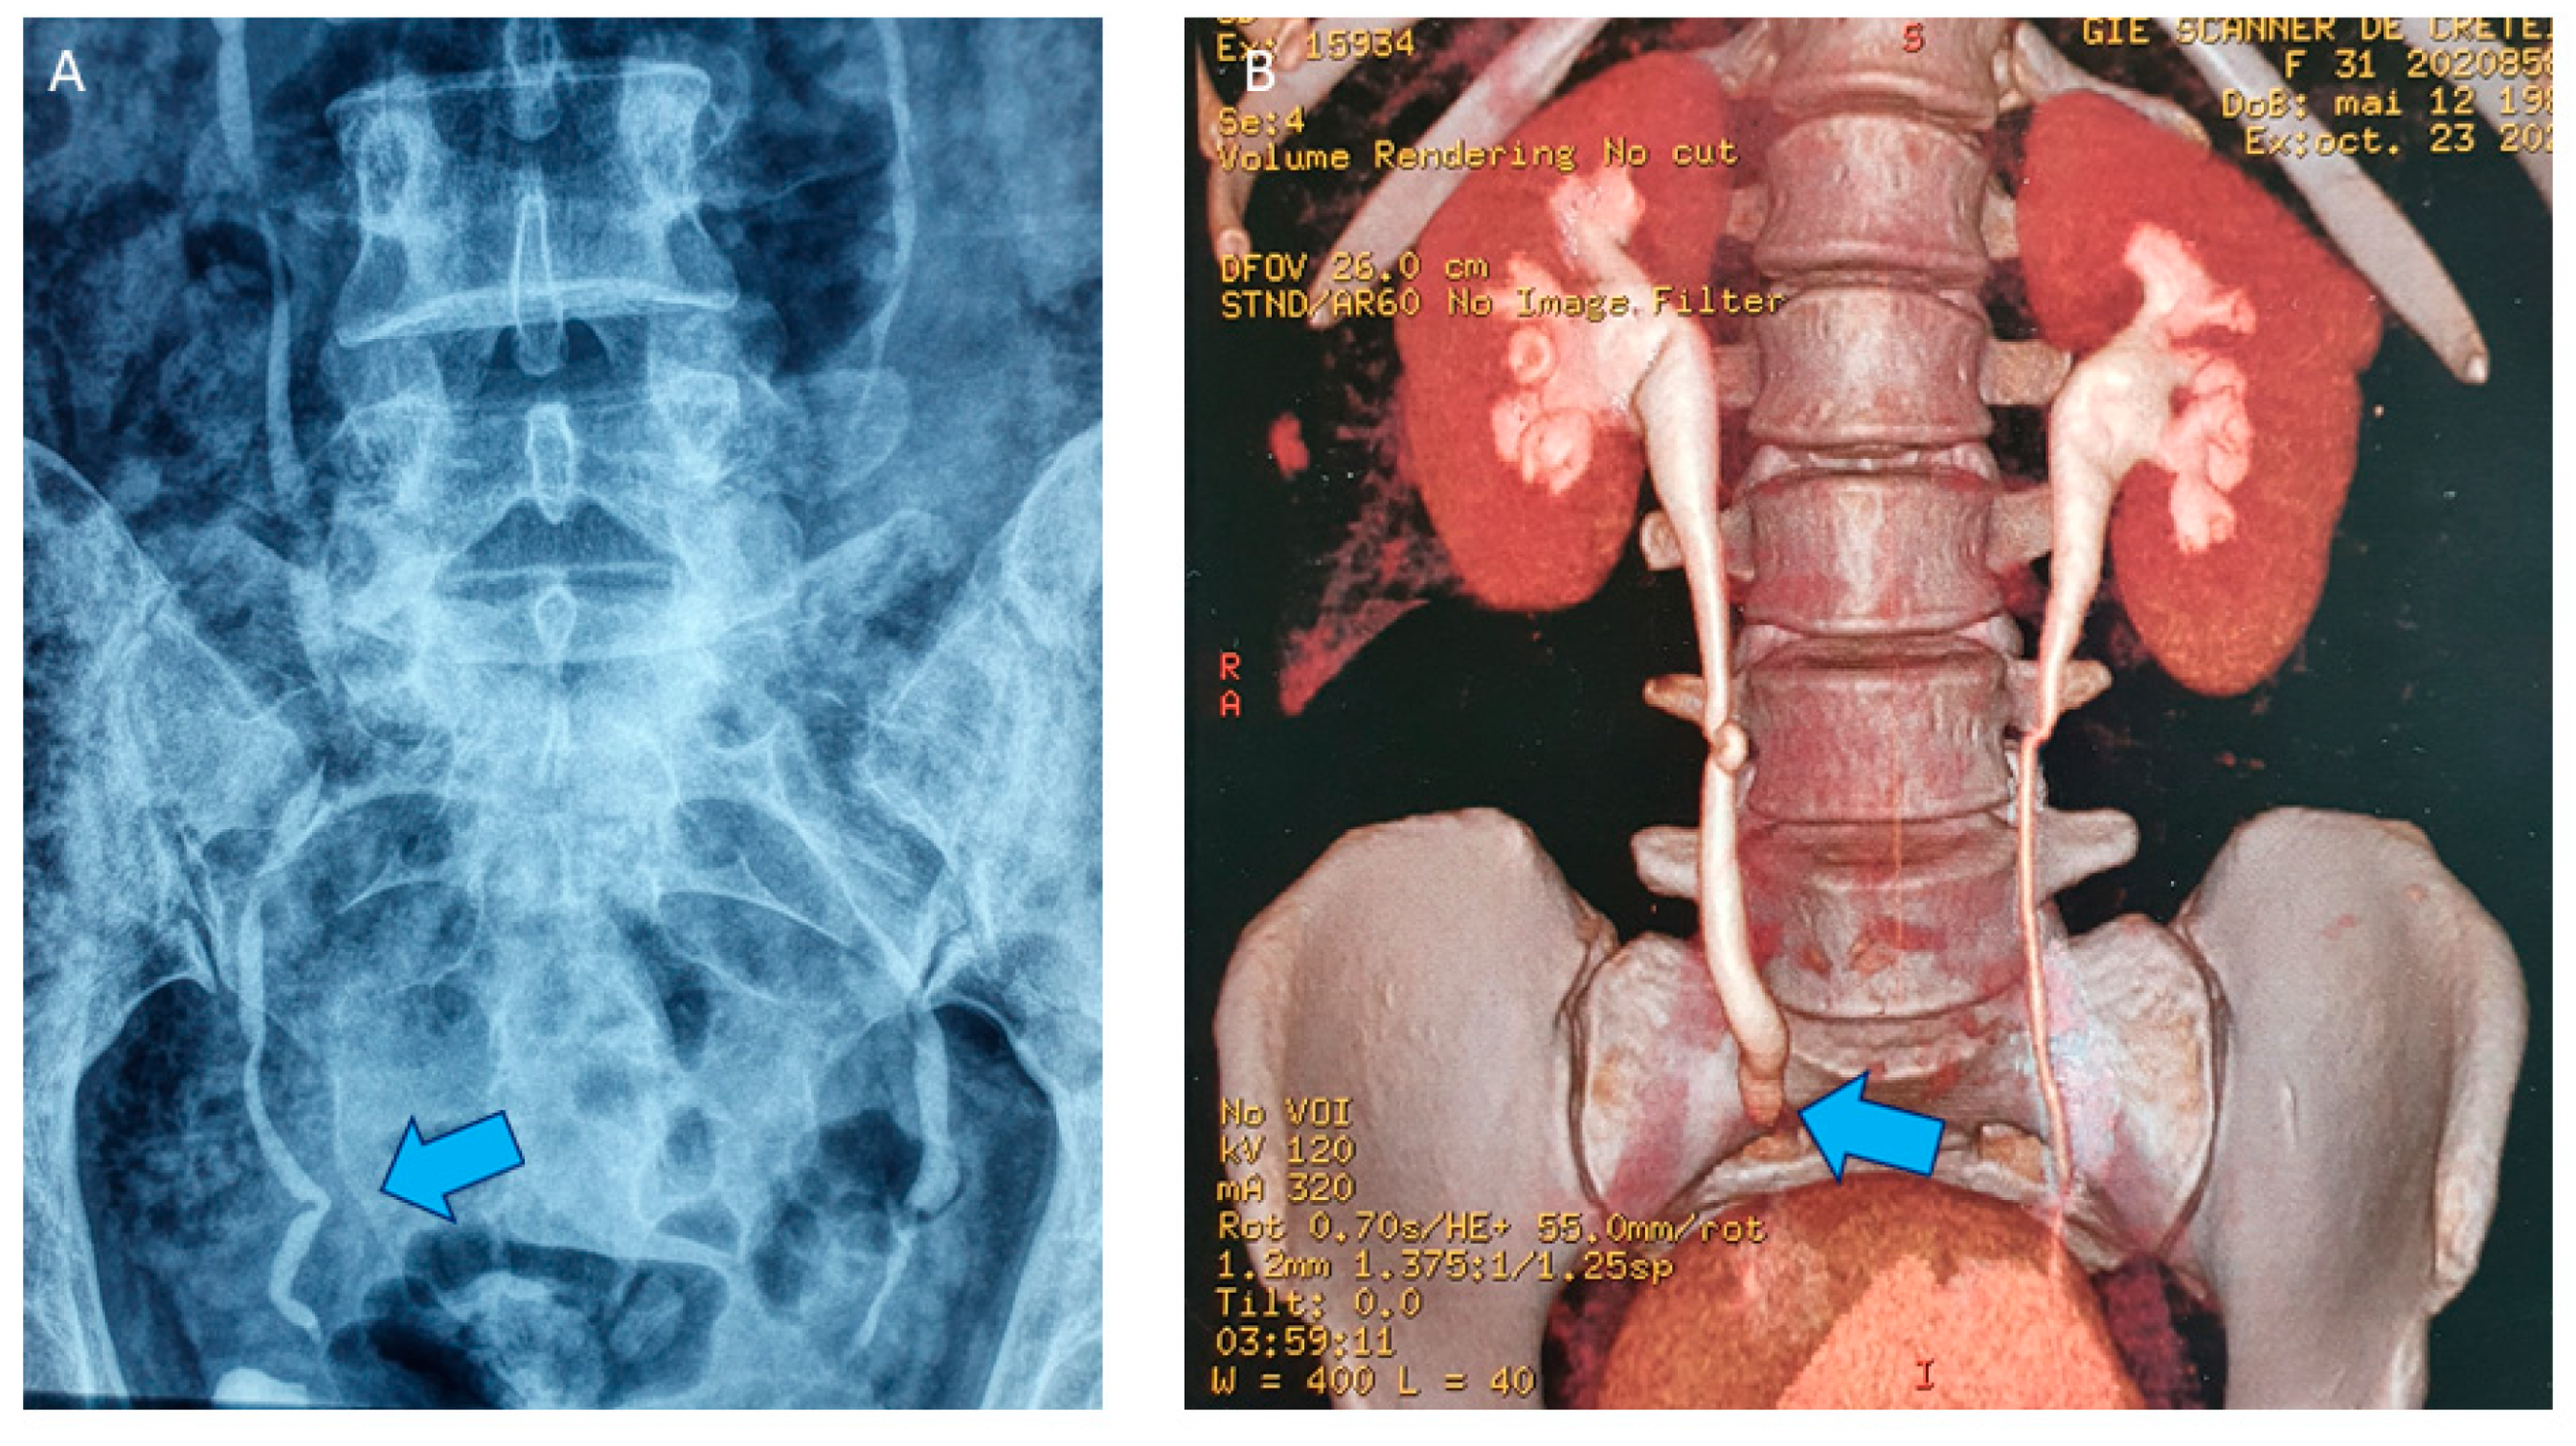

4. Shaving Technique: Surgical Procedure

4.2. Surgical Technique